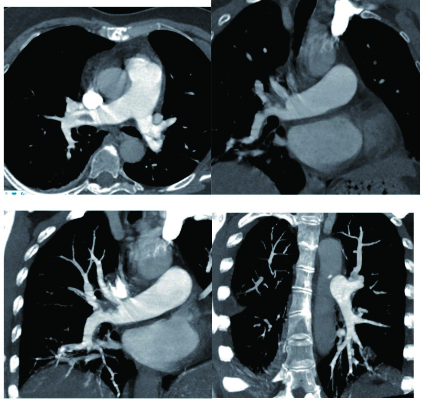

1 经典的挽救性溶栓治疗策略可能带给医生更多的是被动和难度例1 男性,28岁,体质量90 kg。主诉“胸闷、憋气1周加重1 d”。既往:体健;喜久坐(平均10~15 h/d);否认手术史、外伤史;入院查体:神志清楚,体温36.8℃,血压128/80 mmHg(1 mmHg=0.133 kPa),脉搏120次/min,呼吸26次/min,脉氧饱和度96%(安静,空气氧),未见明显乏氧征。双肺呼吸音清,未闻及干湿性啰音。心率120次/min,心律齐,P2 > A2,心界无扩大,无杂音。腹软,无压痛,肠鸣音正常,双下肢无浮肿。神经系统查体未见异常。血气分析(空气氧)提示pH 7.514,PaCO2 27.2 mmHg,PaO2 67.1 mmHg,SaO2 95.0%;D-Dimer:3 035 ng/mL,FDP 33.08 μg/mL,FBG 4.520 g/L;PLT 179.0 G/L,TNI 0.08 ng/mL,BNP 882.00 pg/mL;ALT 38 U/L,AST 17 U/L,CREA 82.6 μmol/L,血Na+、K+、Cl-正常范围;超声心动图(Ultrasonic Cardiogram,UCG)提示:右心增大,肺动脉主干及右肺动脉增宽,肺动脉主干32 mm,三尖瓣反流(重度),反流面积8.6 cm2,TI法估计SPAP为67 mmHg、左室舒末内径50 mm、左室E/A:45/38 cm/s, 左室壁厚度及运动正常,未见节段性室壁运动障碍;双下肢静脉超声提示左侧股静脉血栓形成可能(完全型)。心电图(图 1所示)提示窦性心动过速;肺动脉增强CT(Computed tomographic pulmonary angiography, CTPA)提示双肺主干明确充盈缺损(图 2所示)。入院诊断:急性肺血栓栓塞症(中高危)。入院后给予抗凝治疗(依诺肝素钠90 mg,皮下注射,1次/12 h)重叠华法令治疗的第4天D-Dimer升至47 482 ng/mL,第6天2 411 ng/mL。第7天常规复查双下肢超声未见新增血栓形成,复查UCG(当天INR 2.25)提示右心房漂浮血栓,并随心脏蠕动明显(图 3所示)。在准备胸外科手术取栓的过程中出现血压下降至70/40 mmHg,脉氧饱和度降至45%,立即给予气管插管并系统溶栓治疗(r-tPA 100 mg于2 h输注),溶栓治疗1.5 h患者血压逐渐回升并趋于稳定、溶栓治疗3 h自主呼吸开始恢复,于插管3天后(住院第10天)拔出气管插管,成功撤离呼吸机。溶栓过程中曾经出现消化道、气道出血,血红蛋白下降1.9 g/dL,未予输血治疗。溶栓后复查CTPA提示双肺主干血栓负荷明显减少,远段血液灌注明显增加(图 4所示)。

| 图 2 入院时CTPA提示双肺主干明确充盈缺损 |

| 图 4 溶栓后的CTPA肺动脉主干血栓负荷明显减少、远段血液灌注明显增加 |